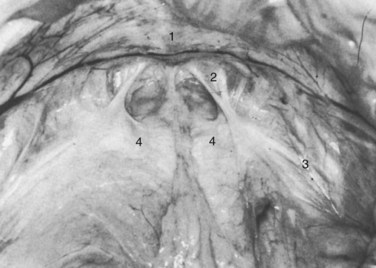

Figure 2–11 Floor of the space of Retzius in a thin, elderly female cadaver. The fat has been removed to show the continuous sheet of endopelvic fascia, and the bladder has been retracted posteriorly. 1, Symphysis pubis; 2, right pubourethral ligament; 3, lateral condensation of endopelvic fascia forming the right arcus tendineus fasciae pelvis; 4, condensation of the endopelvic fascia, which forms a firm, whitish aponeurosis over the proximal urethra and internal vesical orifice.

(From Mostwin JL. Current concepts of female pelvic anatomy and physiology. Urol Clin North Am 1991;18:178.)